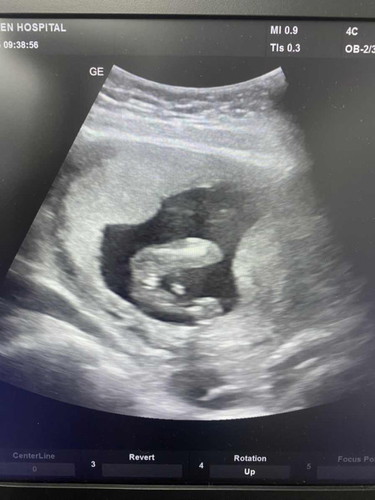

หมอบอกน่าจะผญค่ะ แต่ยังไม่ชัด เพราะคุณหมอบอกไม่เห็นแท่งยื่นออกมาแต่ก็ไม่100%